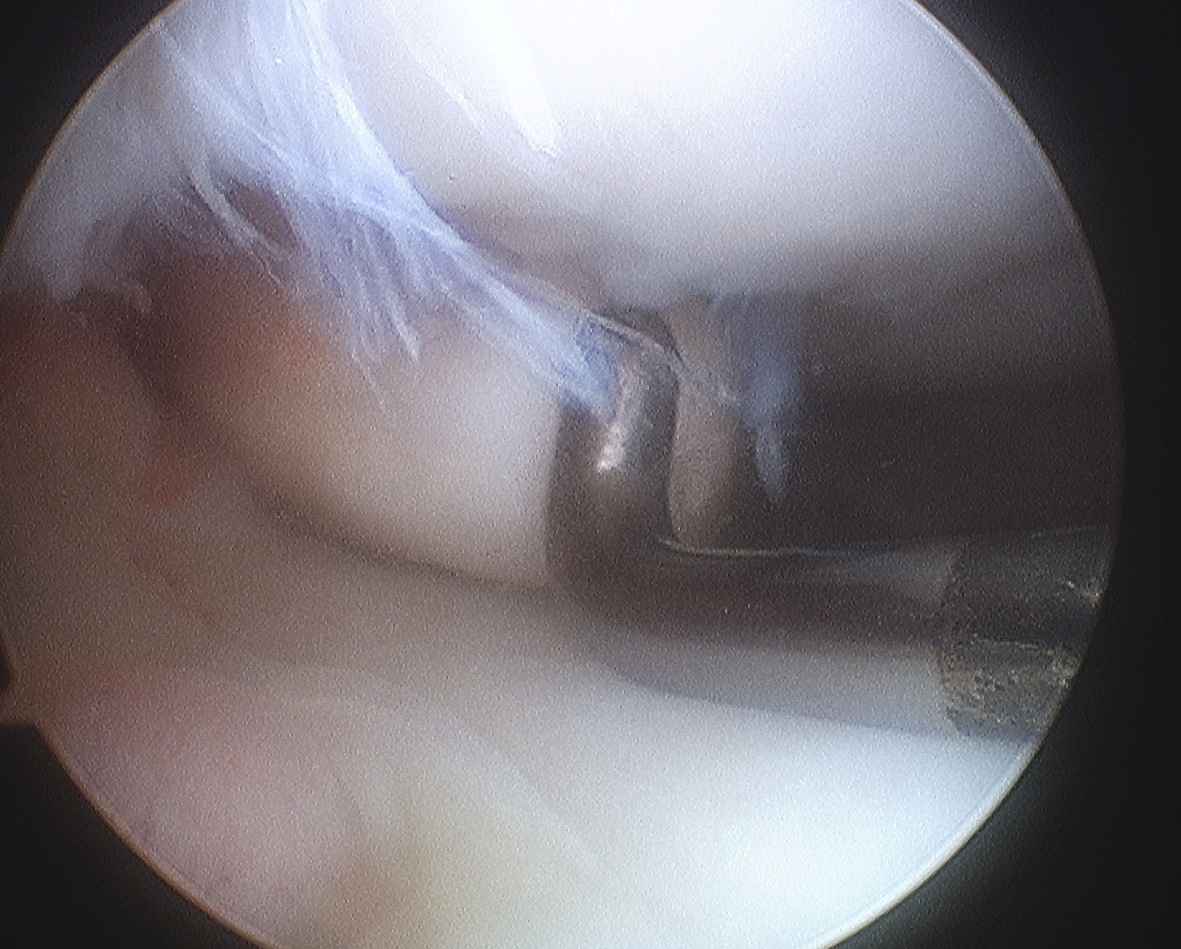

ICRS Arthroscopic Classification

3. Completely detached but insitu

4. Fully detached with crater & loose body

A. Chondral Fragment Salvageable

- recent

B. Chondral fragment unsalvageable

- increased in size / change in shape